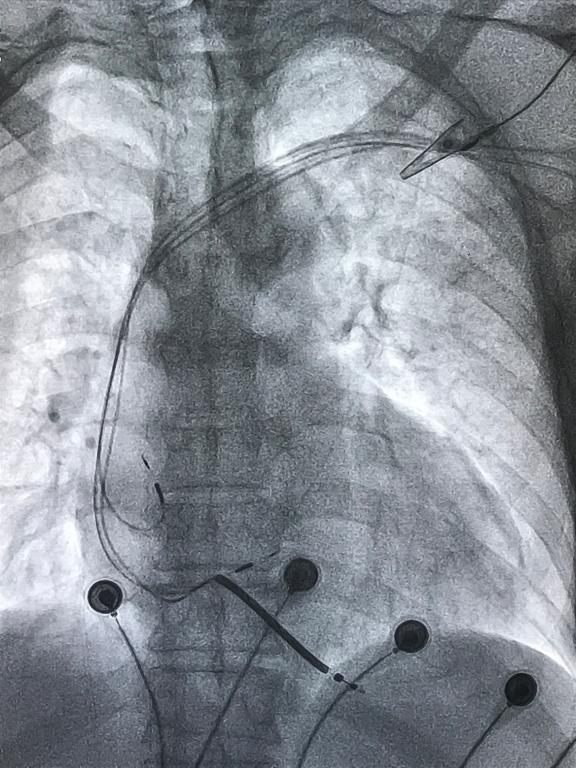

每一次技术的进步均来于勇于探索和创新,绵绵的南方细雨在2月24日这天露出了久违的阳光。夏中华带领心血管内科的医护人员披上铅衣、全副武装,在介入室内为患者开展手术,2个小时后,左束支起搏的永久起搏器植入术顺利完成!

术后监测各项指标良好,起搏器工作正常,患者心衰症状明显改善,手术十分成功,将于近期出院。